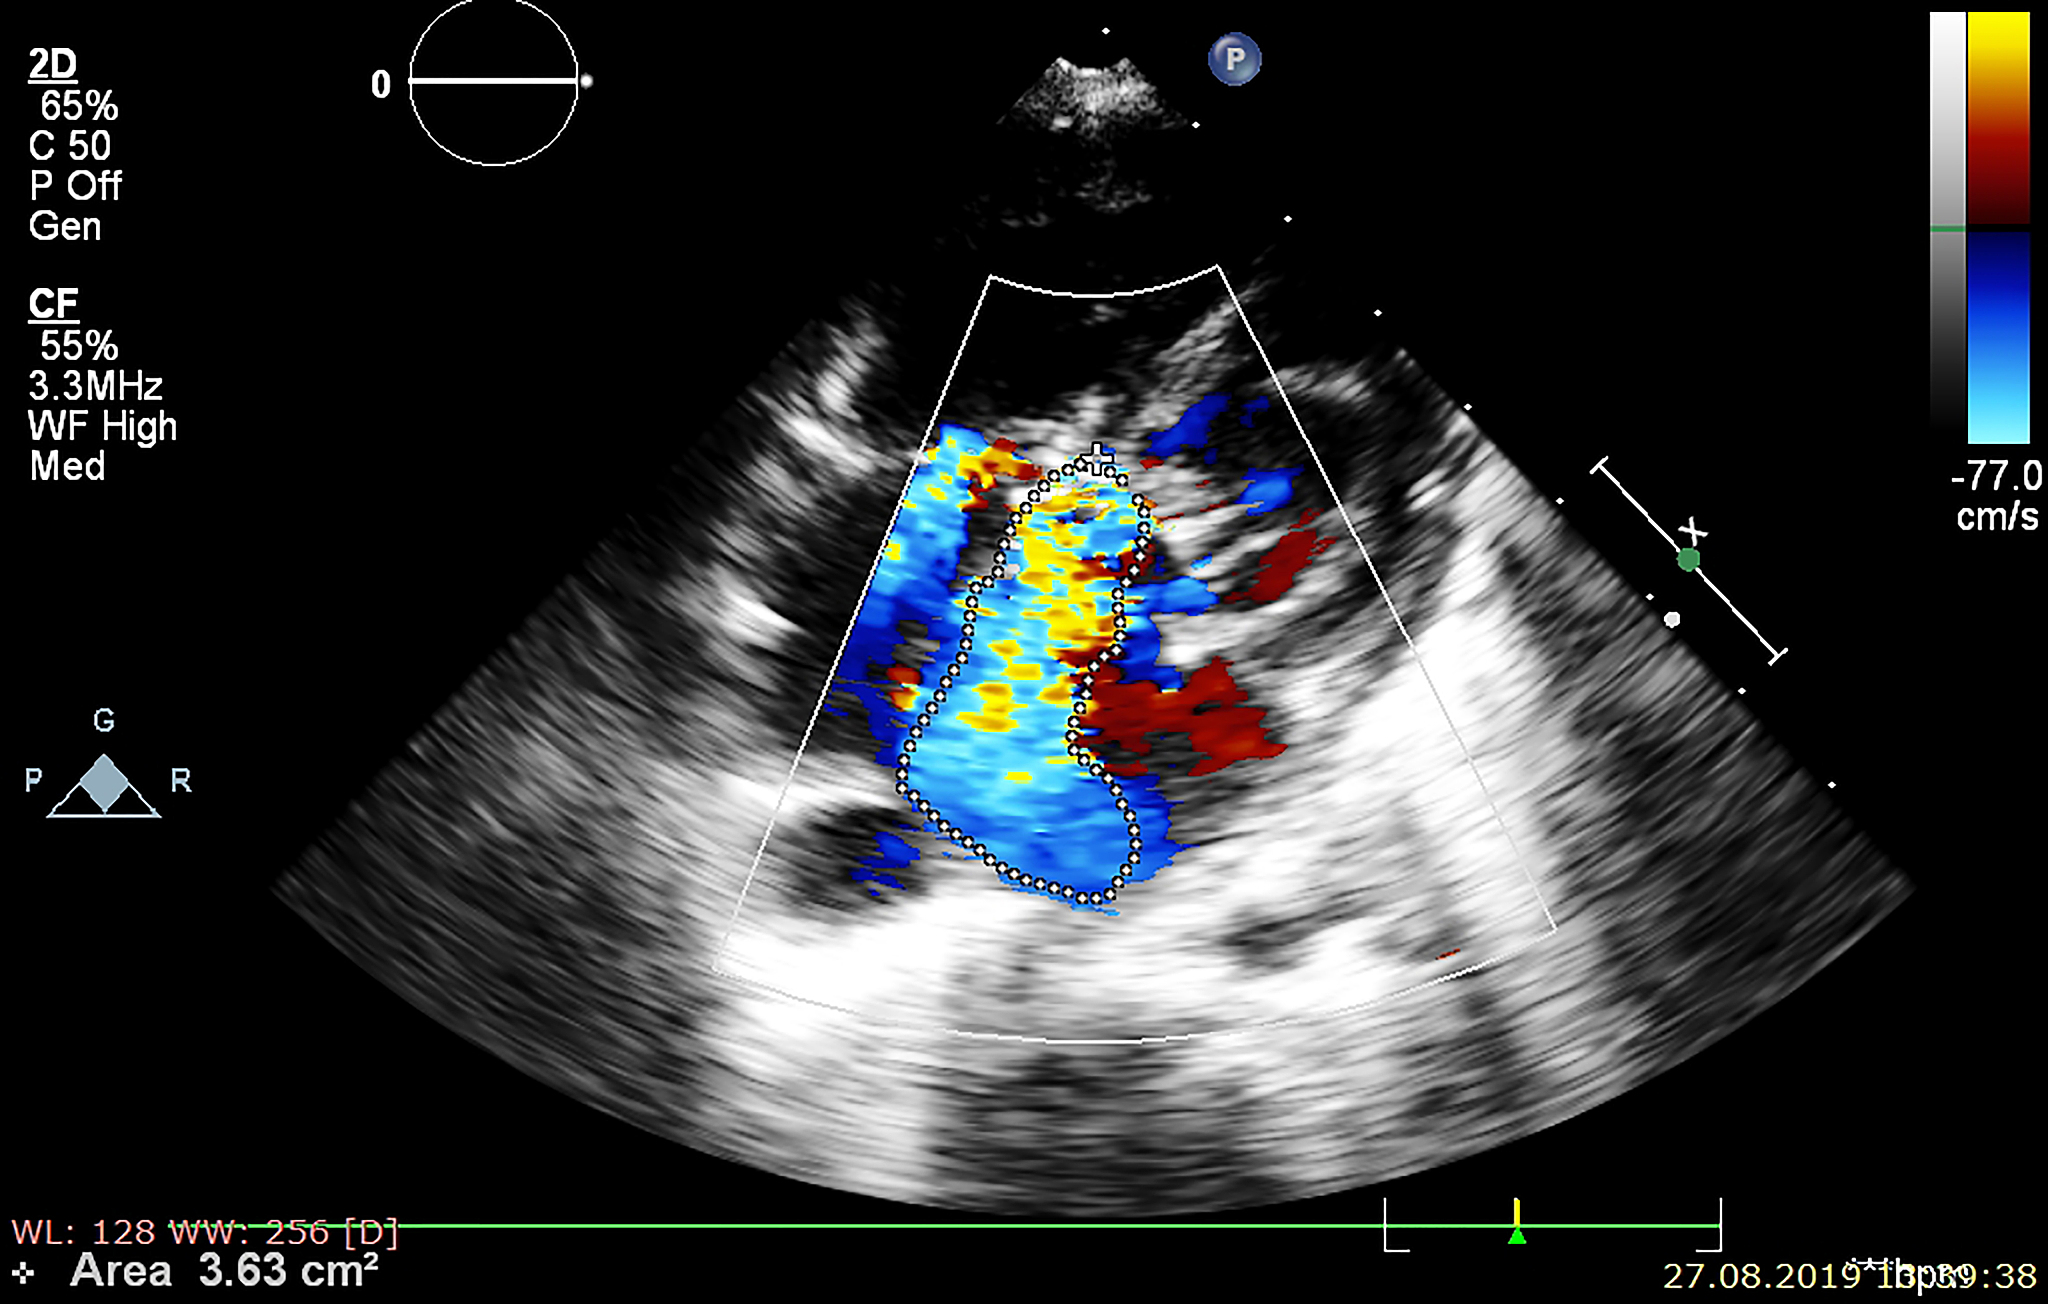

Translation: Comparative study of transthoracic echocardiography and transesophageal echocardiography combined with right heart acoustic imaging for the diagnosis of patent foramen ovale (PFO), and evaluation of the optimal diagnostic strategy.

卵圆孔未闭 (PFO) 诊断:经胸超声心动图、经食道超声心动图和右心声学造影的对比研究